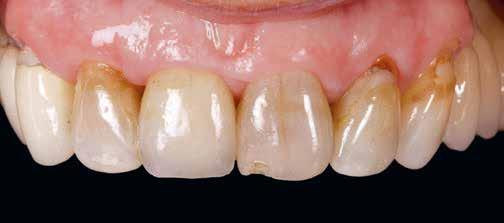

mmMT3,

± 0.480.26 ± 0.540.35 ± 0.590.40 ± 0.80

Legyen Ön is a VIP Dental partnere!

Szeretne folyamatos, kiszámítható és tervezhető, passzív bevételre szert tenni?